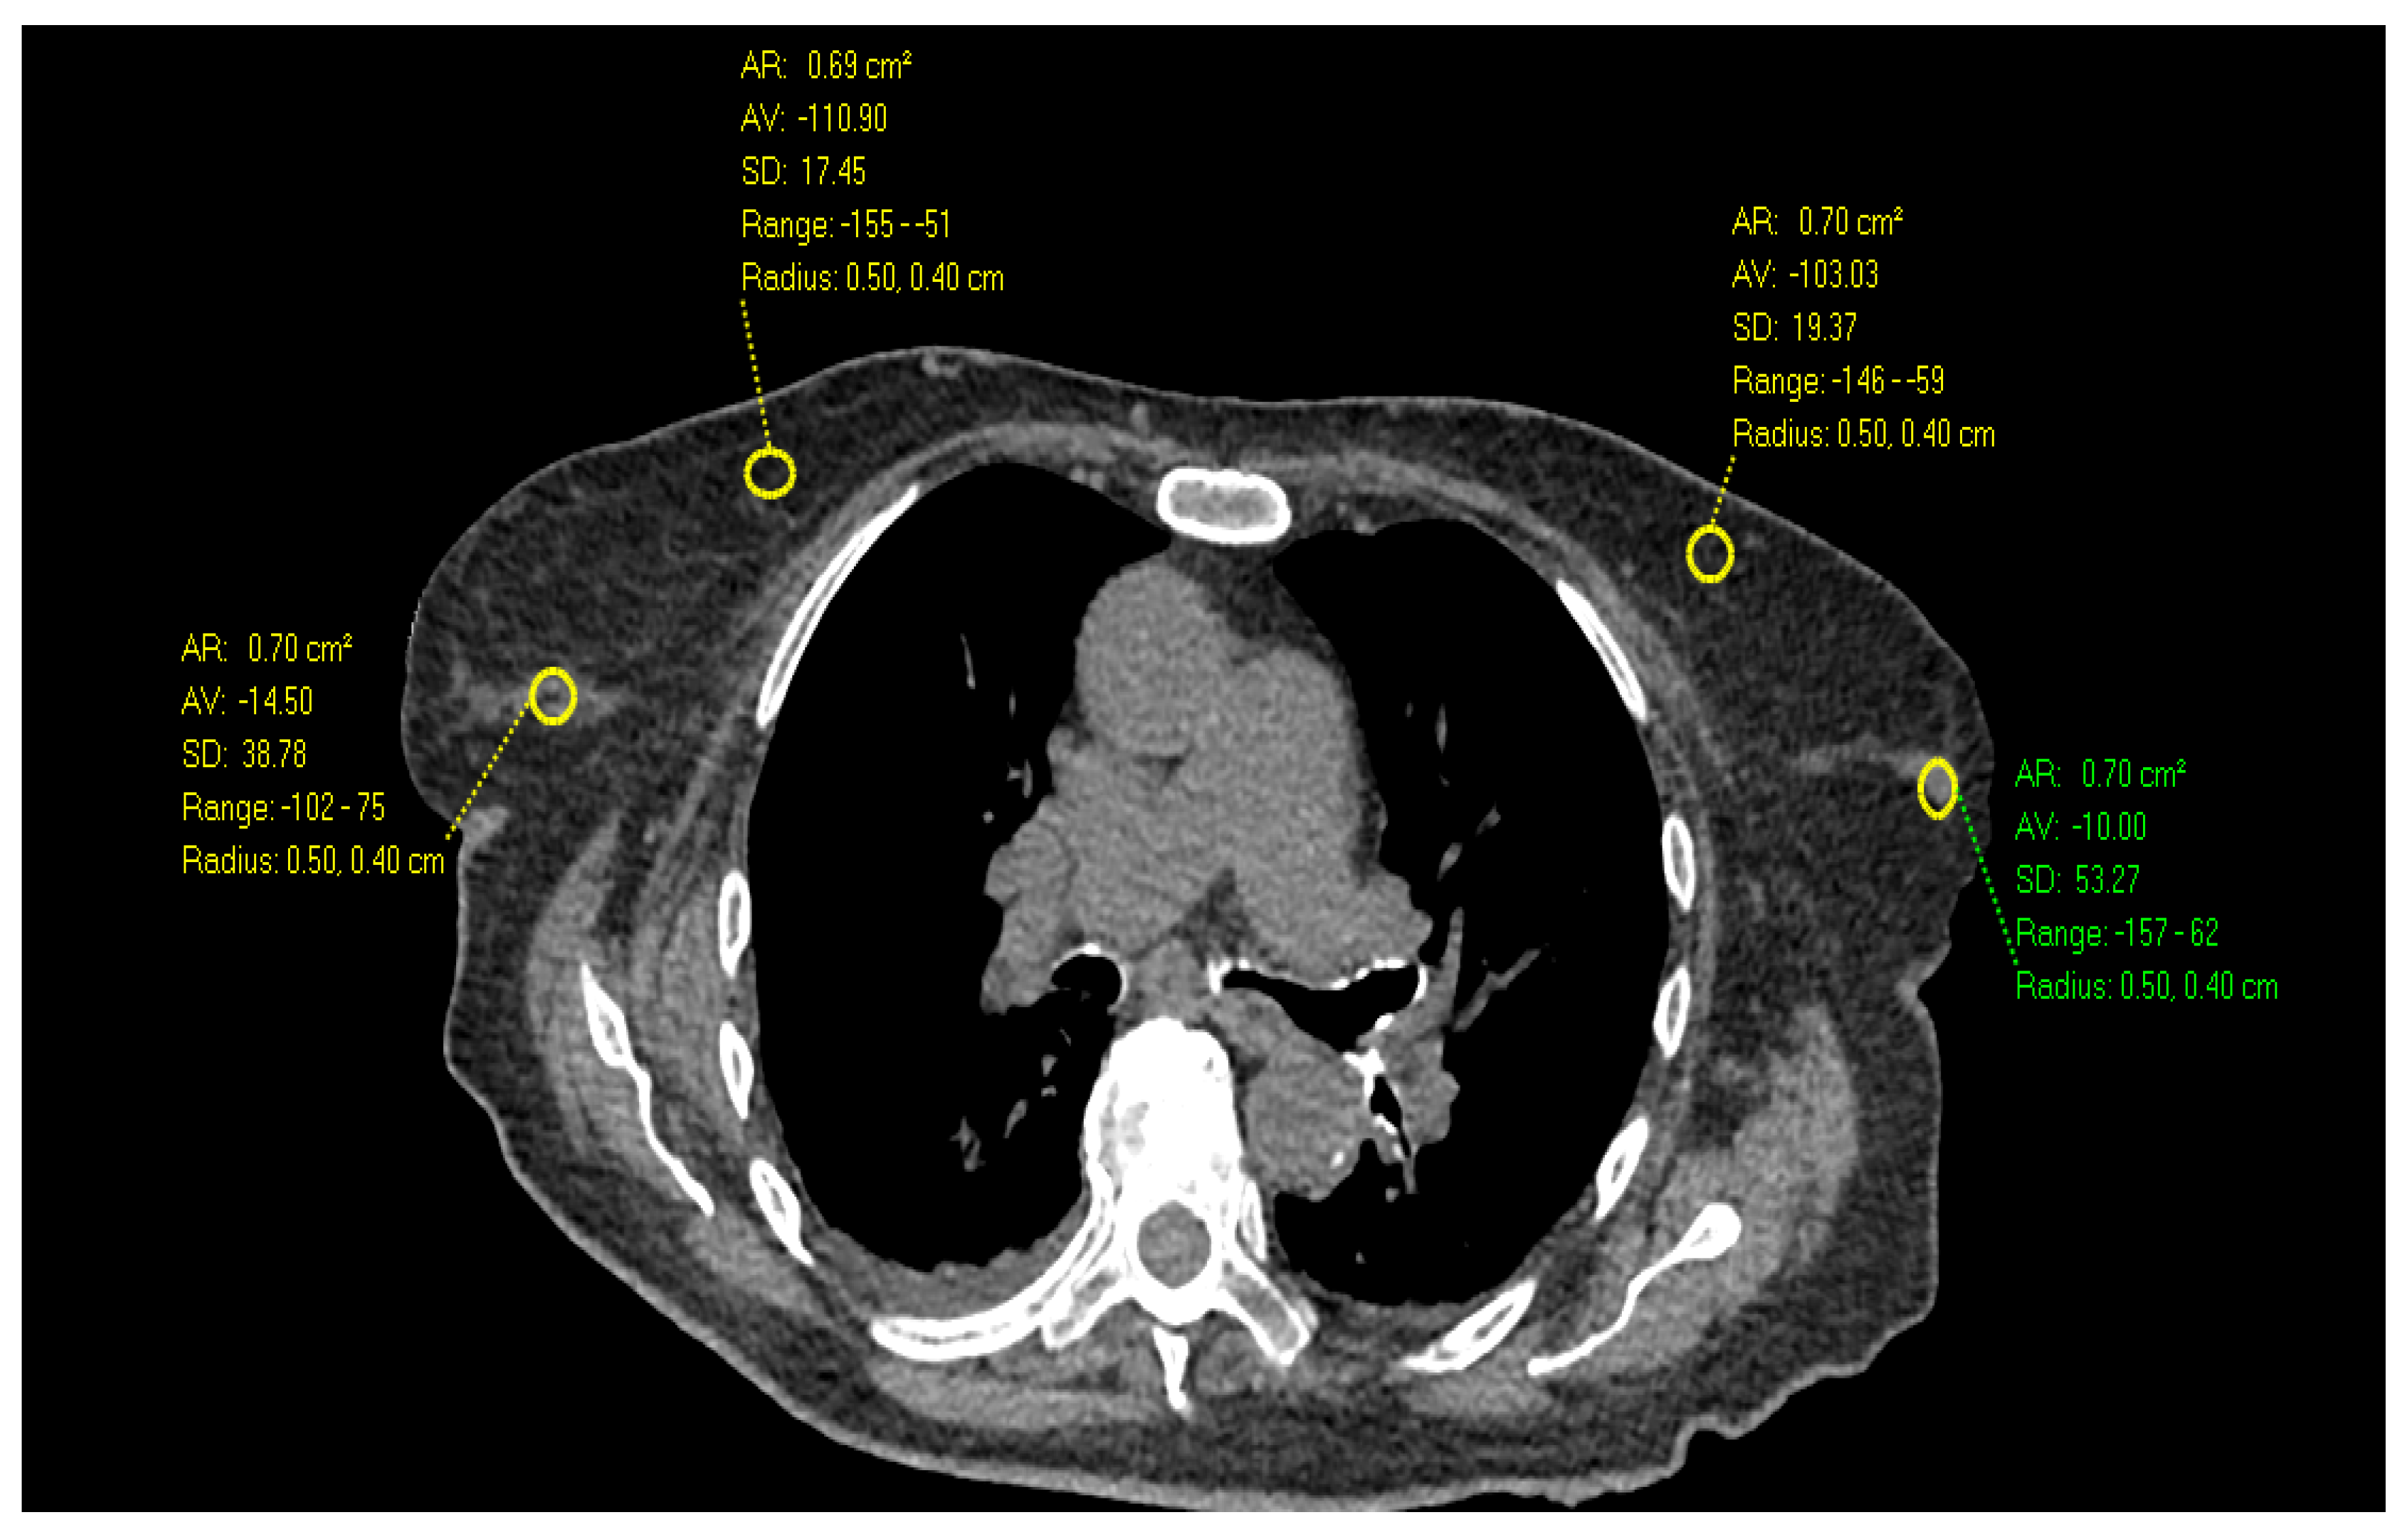

2. Materials and Methods

- Desperito, E.; Schwartz, L.; Capaccione, K.M.; Collins, B.T.; Jamabawalikar, S.; Peng, B.; Patrizio, R.; Salvatore, M.M. Chest CT for Breast Cancer Diagnosis. Life 2022, 12, 1699. [Google Scholar] [CrossRef] [PubMed]